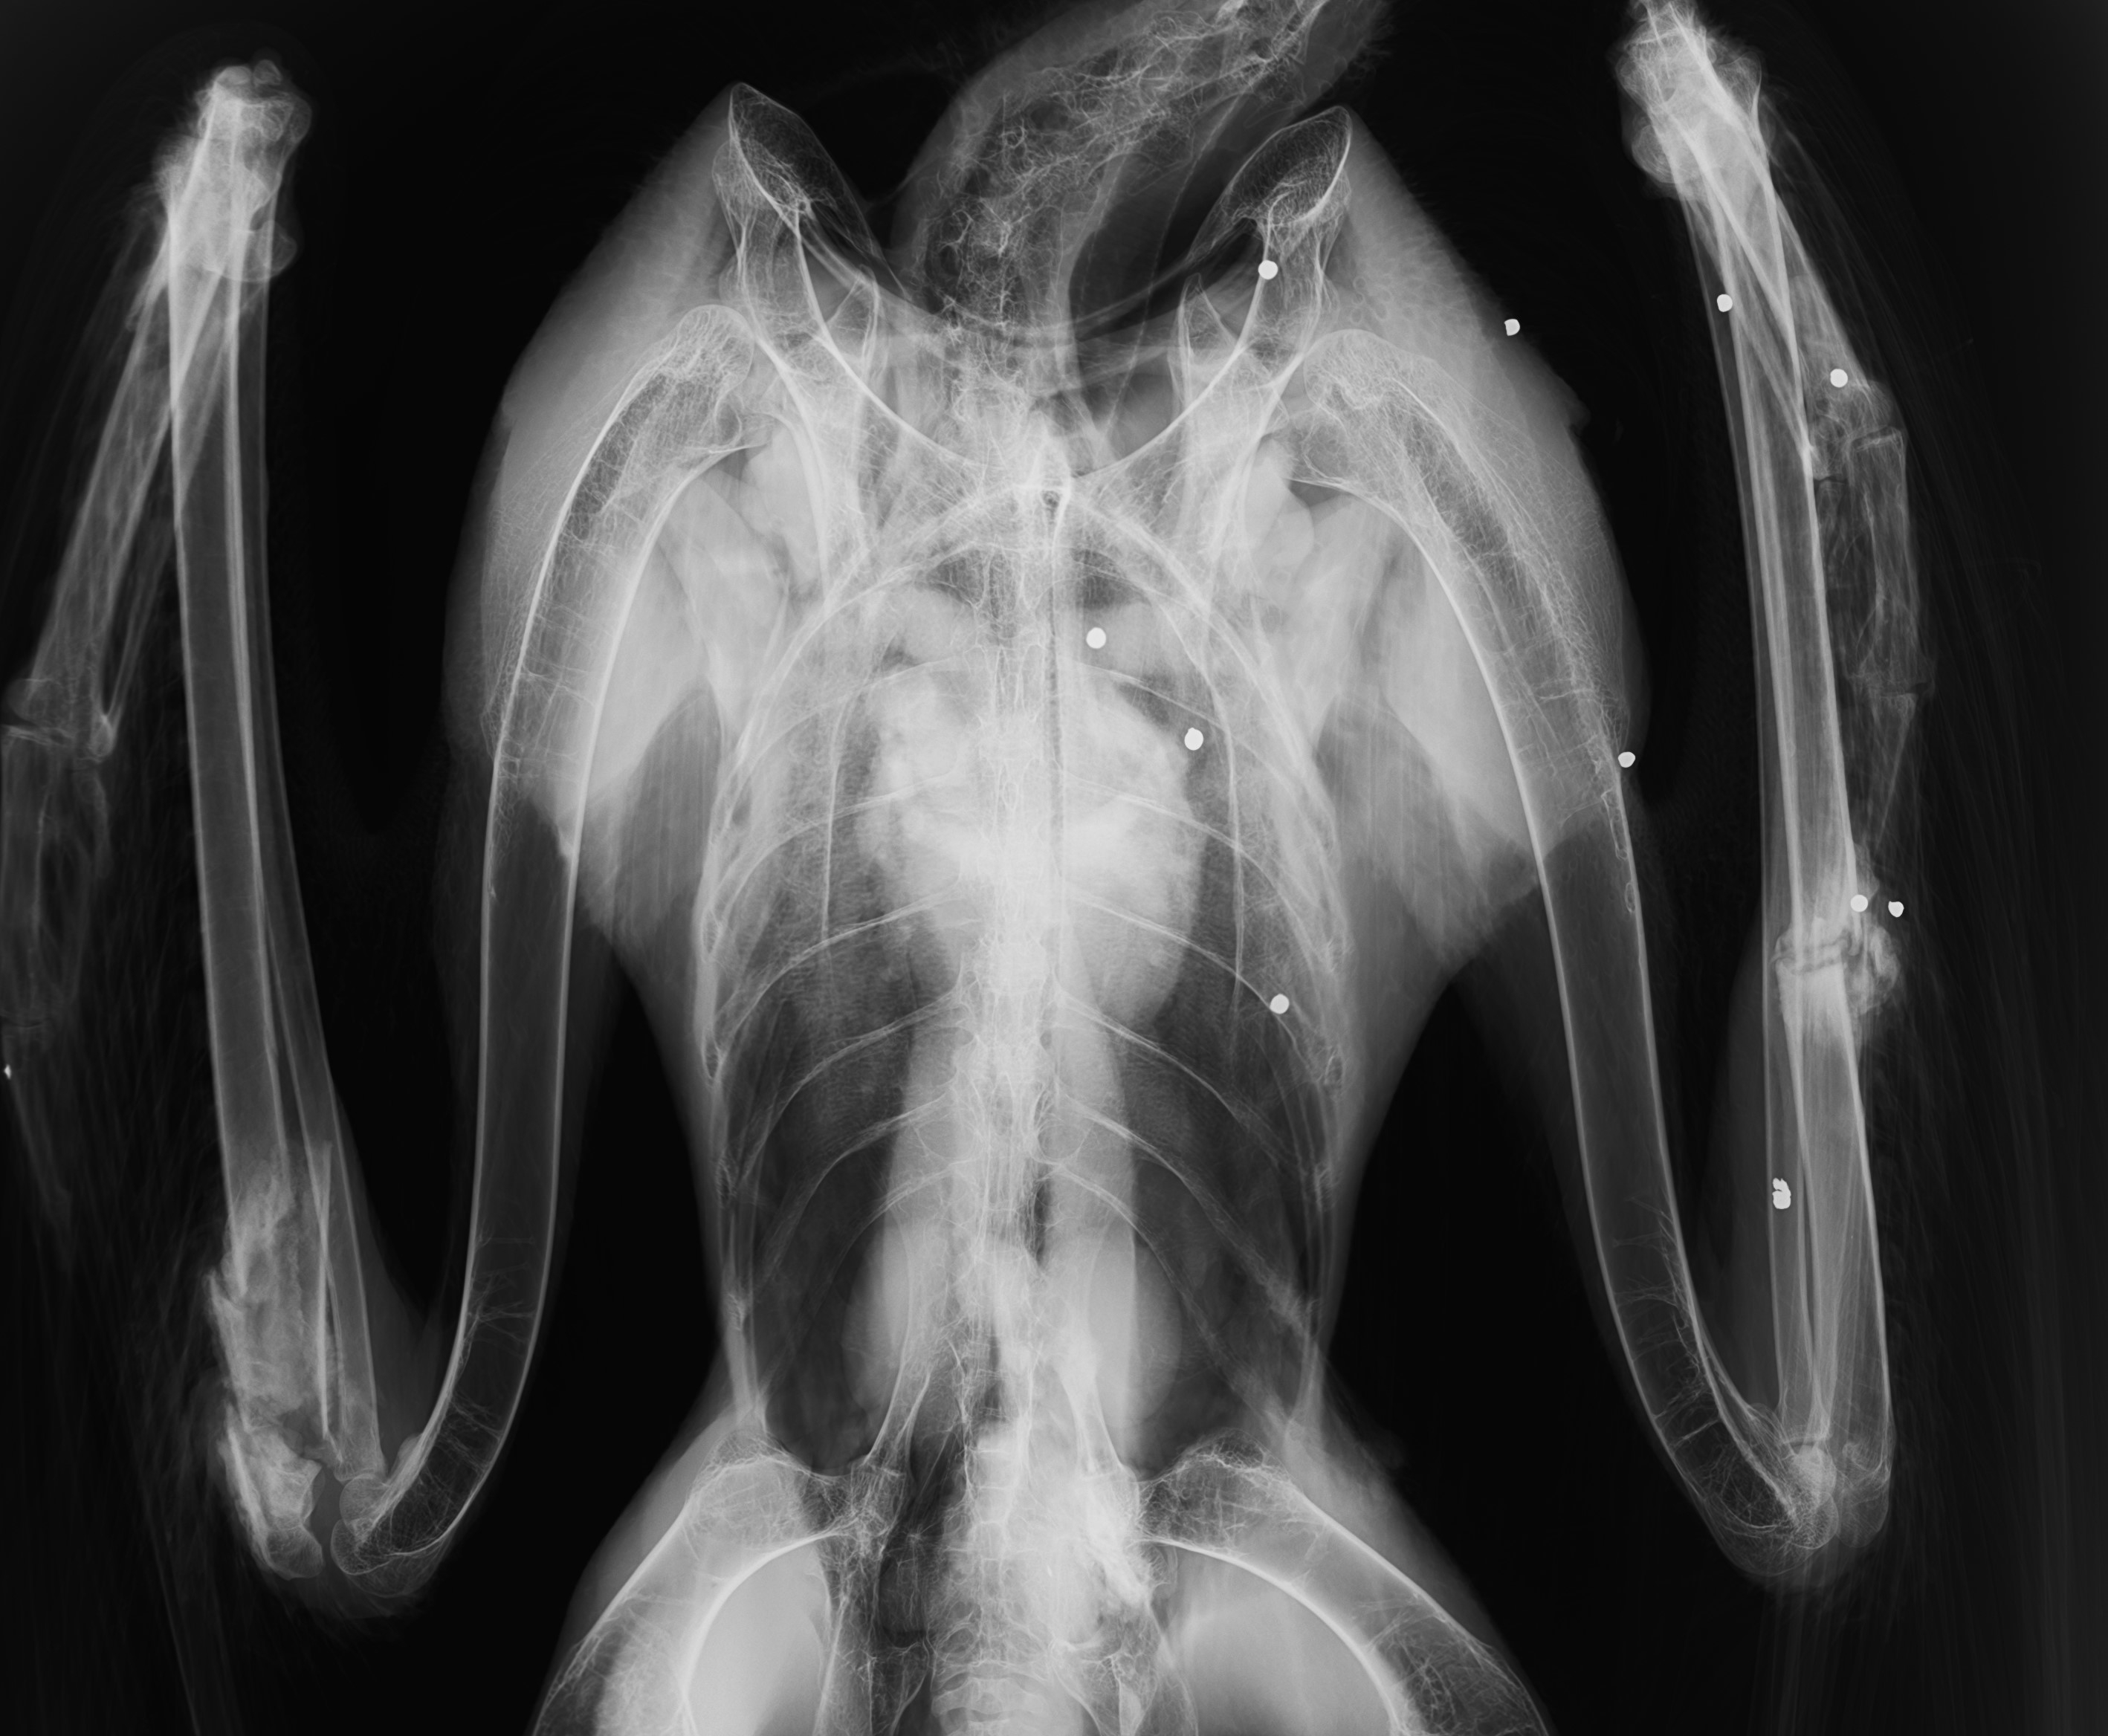

- 左右の翼に骨折が見られる他、頭部から左半身にかけて約20粒の散弾を被弾している。被弾した散弾は、大きさや体内での変形状況から水鳥や小中型獣猟用に用いられる鉛散弾の可能性が高い。

- 傷の状態から、受傷から1ヶ月程度経過していると推測される。

- 左翼の骨折は患部に存在する散弾を被弾したことによると思われる。右翼の骨折については、周辺に被弾が認められないことから、銃撃を受けた際の高所からの墜落のほか、被弾後に車や列車などと衝突したことによる可能性も考えられる。

写真:被弾したオオワシのレントゲン写真(猛禽類医学研究所提供)